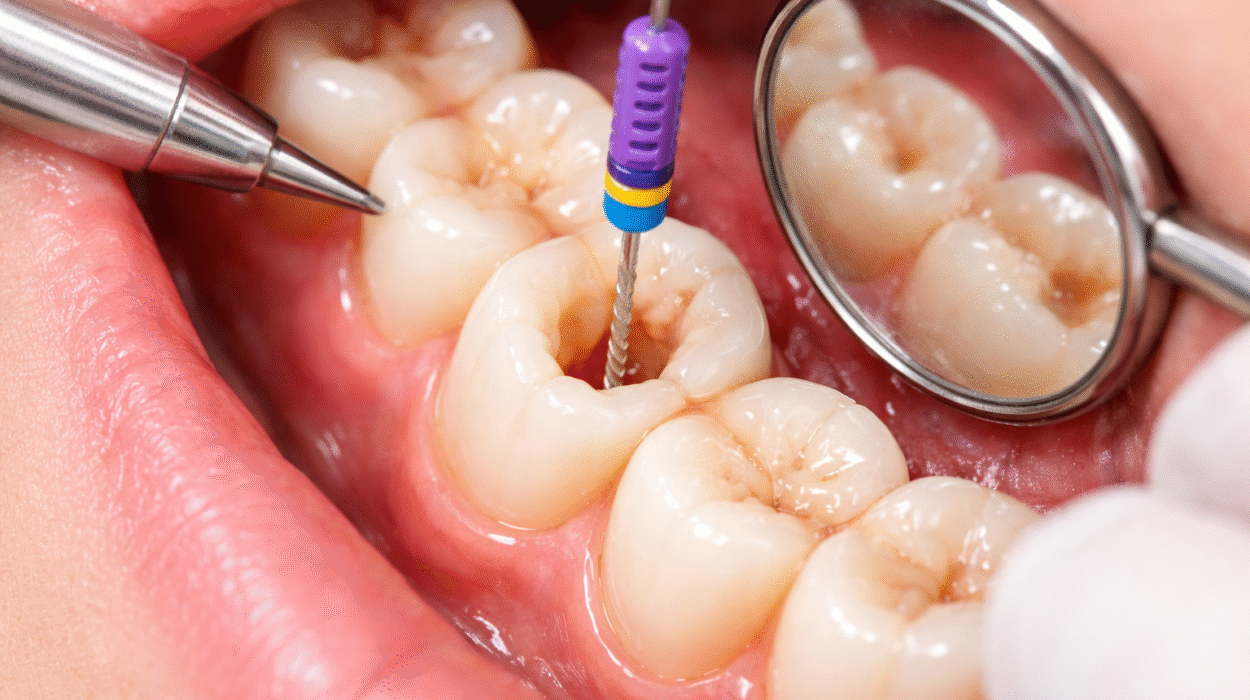

ببساطة طبية دقيقة، علاج قناة الجذر هو إجراء يهدف إلى إزالة اللب الملتهب أو المصاب داخل السن، ثم تنظيف القنوات الجذرية وتعقيمها وإغلاقها بإحكام لمنع عودة البكتيريا. اللب هو النسيج الداخلي الذي يحتوي على الأعصاب والأوعية الدموية، وعندما يتعرض للتلف نتيجة تسوس عميق أو كسر أو صدمة، يصبح مصدرًا للالتهاب والألم.

بعد ذلك يتم عزل السن باستخدام حاجز مطاطي لمنع تلوثه أثناء الإجراء. ثم تُستخدم أدوات ميكانيكية حديثة لتنظيف القنوات بدقة متناهية. وفي حالات العدوى الشديدة، قد يضع الطبيب دواءً داخل القنوات لبضعة أيام قبل الإغلاق النهائي.

- فتح جزء بسيط من تاج السن للوصول إلى القنوات.

- إزالة اللب الملتهب باستخدام أدوات دقيقة.

- تنظيف وتوسيع القنوات وتعقيمها.

- حشو القنوات بمادة خاصة تمنع التسرب البكتيري.

في المراكز المتطورة، يُستخدم الميكروسكوب الطبي لزيادة الدقة، وهو ما يرفع نسبة النجاح بشكل ملحوظ.